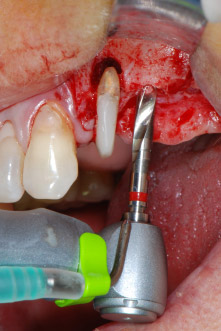

En primer lugar, en un intento por gestionar el problema endo-periodontal, el resto de la superficie radicular se desbridó con cuidado con un equipo piezoeléctrico (Piezomed de W&H, utilizado con el inserto S1 con forma de espátula, concebido en un principio para la erosión de la pared lateral del seno) (figura 4). A continuación, el ápice se erosionó con el mismo instrumento para eliminar el tejido apical infectado residual y reducir las posibles ramificaciones accesorias del canal radicular (apicectomía) (figura 5). No fue necesario realizar un retrorellleno, puesto que la obturación ortógrada se acababa de revisar.

Fig. 4: Para conservar el diente como un pilar provisional, el periodontio se desbridó utilizando un equipo piezoeléctrico...

ápice bucal

Fig. 5: ... y el ápice bucal de la pieza 24 se erosionó con el mismo inserto (apicectomía).